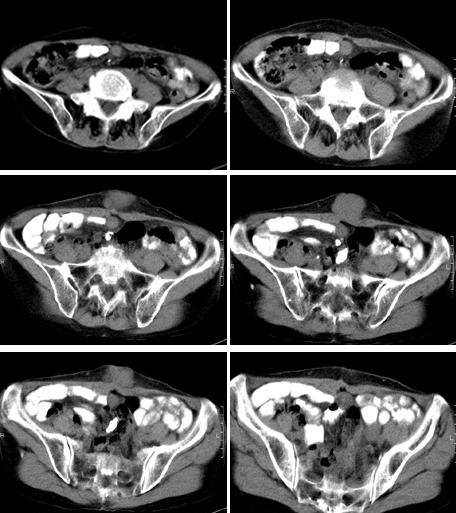

女,65岁,三月前发现腹部包快,无临床症状。

腹壁见多个软组织块影,边缘清楚,以硬纤维瘤和脂肪瘤常见。血管瘤,神经性肿瘤均少见。脂肪瘤有脂肪影,可排除。考虑硬纤维瘤。

因为没有强化扫描和详细的临床情况{如肿块是否有移动,按压痛}对肿块是否是淋巴结组织或实性组织的判断带来困难。病灶位于腹白线和腹股沟旁{而且是对称分布!},首先应该考虑是淋巴结,至于是何种原因引起的淋巴结肿大只能结合临床考虑。另外要考虑到3楼战友分析的硬纤维瘤{属于良性},还有腹壁续发性肿瘤它也具有沿淋巴转移的特点。

腹壁皮下脂肪内及双侧腹股沟区多发软组织密度肿块,肿块形态不规则,与皮肤粘连,根据其多发的特点,结合患者为老年女性,三月前新发病灶,应该首先考虑为转移性病变,应积极寻找原发癌瘤。

前腹壁皮下及两侧腹股沟多发结节,境界清晰,周围脂肪间隙清晰,考虑良性病变,硬纤维瘤。

腹壁及腹股沟区软组织肿块,肿块较大无包绕血管征,边界较清楚,.

考虑1间叶组织肿瘤。2转移瘤待排。